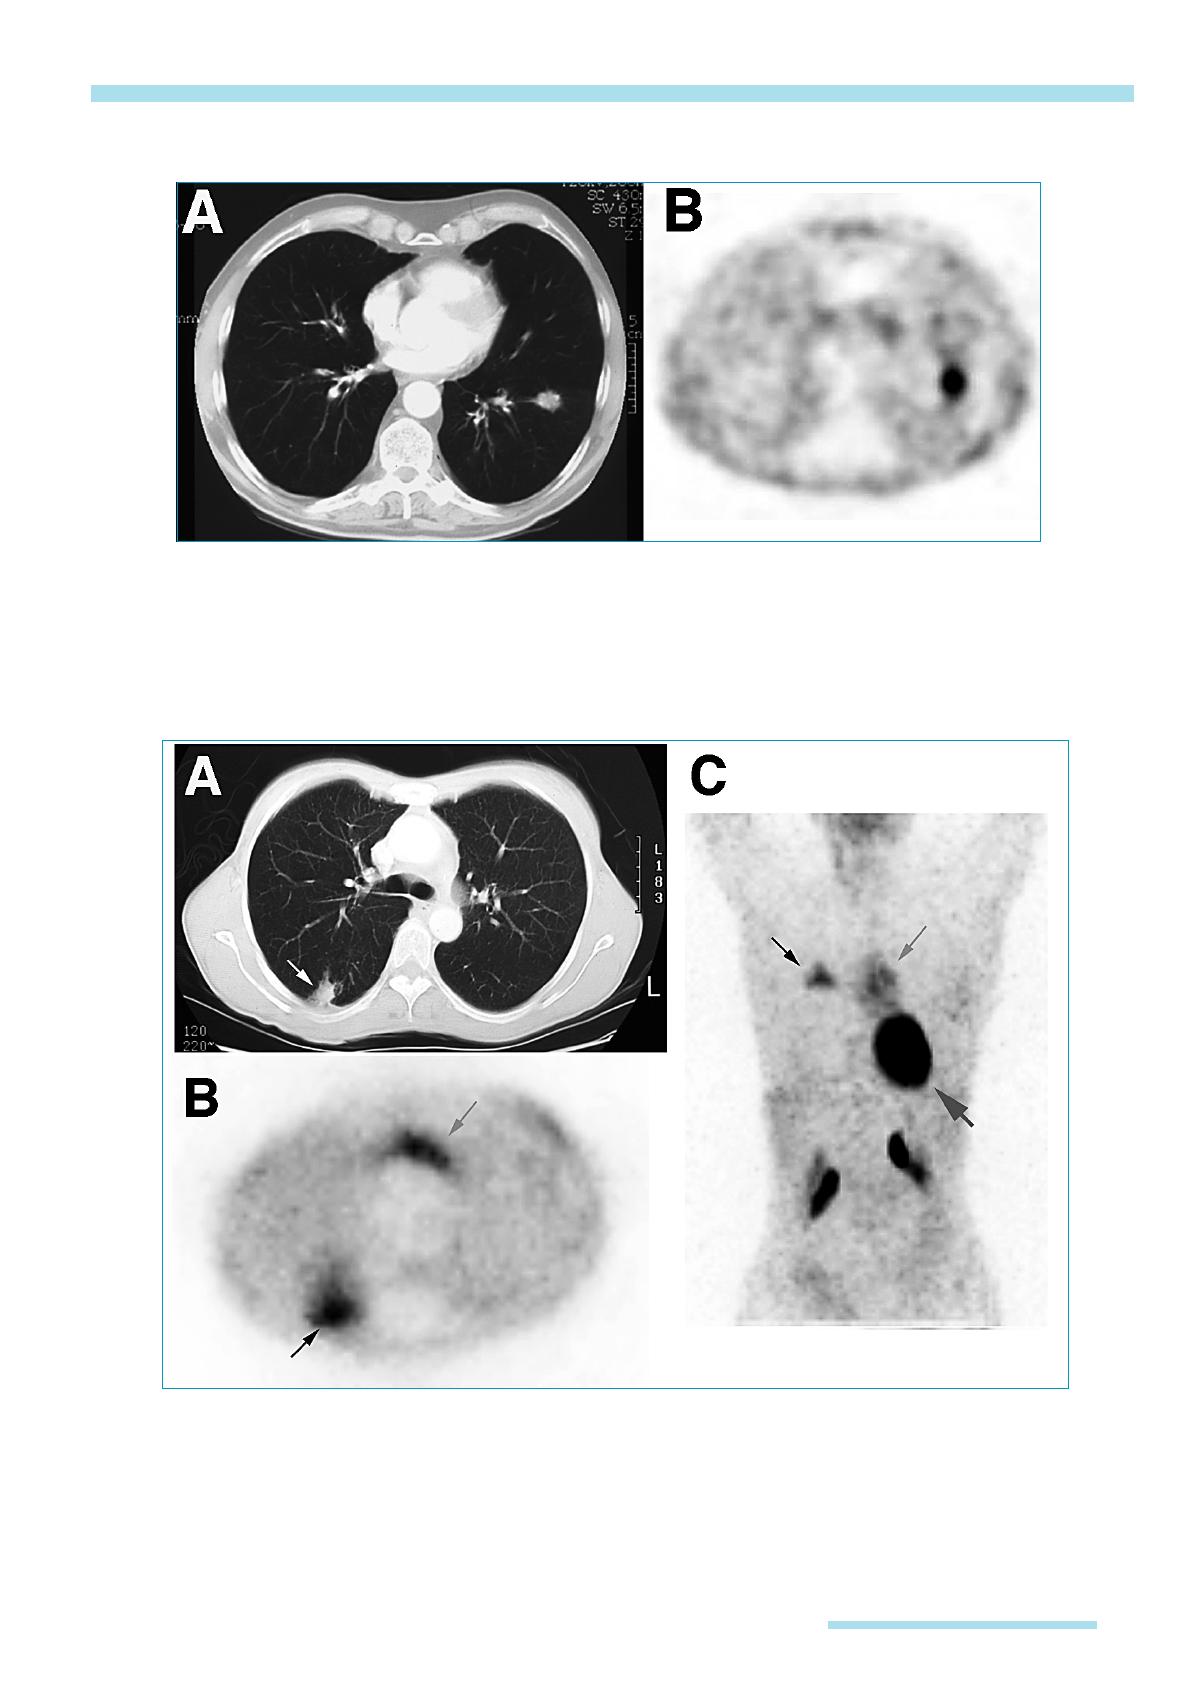

Pour améliorer les performances de

l’imagerie au FDG, on peut essayer

d’augmenter le pouvoir discriminant

de la technique, en réalisant des étu-

des en deux temps. Le principe de la

sensibilisation de la méthode est d’uti-

liser la différence de captation entre

les cellules normales et les cellules

tumorales qui atteignent un plateau

de fixation souvent plus tardivement

que les cellules normales. Pour les

patients dont la fixation des nodules

est proche du seuil de 2,5 SUV, on

peut mesurer la captation du FDG, une

heure et trois heures après l’injection.

La fixation relative du FDG augmente

dans les lésions malignes et reste sta-

ble ou légèrement décroissante dans

les lésions non tumorales [24]. Dans

une étude sur 36 patients porteurs de

nodules pulmonaires et en utilisant

une valeur seuil de variation de 10 %

entre la captation précoce et tardive,

la sensibilité de l’imagerie TEP passe

de 80 à 100 %, au prix d’une diminu-

tion de la spécificité de 94 à 89 % [20].

L’augmentation de la fixation

médiastinale pourrait améliorer aussi

l’exactitude du bilan d’extension gan-

glionnaire dans le médiastin [25].